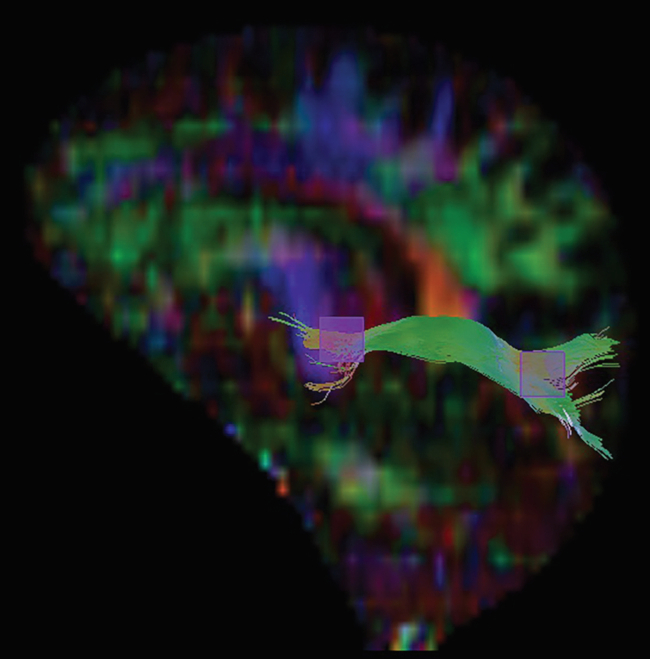

Implicado con el sistema límbico, este fascículo posee fibras en U y de proyección. Las primeras llevan la dirección de todo el giro del cíngulo formando una especie de arco, conectando áreas del prefrontal hasta la zona parahipocampal, alcanzando el uncus del lóbulo temporal. Las fibras en U que inician en el área subcallosa y se conectan con el lóbulo frontal, parietooccipital y temporal. Los dos ROI para ese fascículo se obtuvieron en corte sagital del mapa de anisotropía (►Figura 5).

FC derecho sobre un fondo de mapa de AF en corte sagital. Con la técnica cuboide se hizo la siembra en dos ROI en la región frontal.